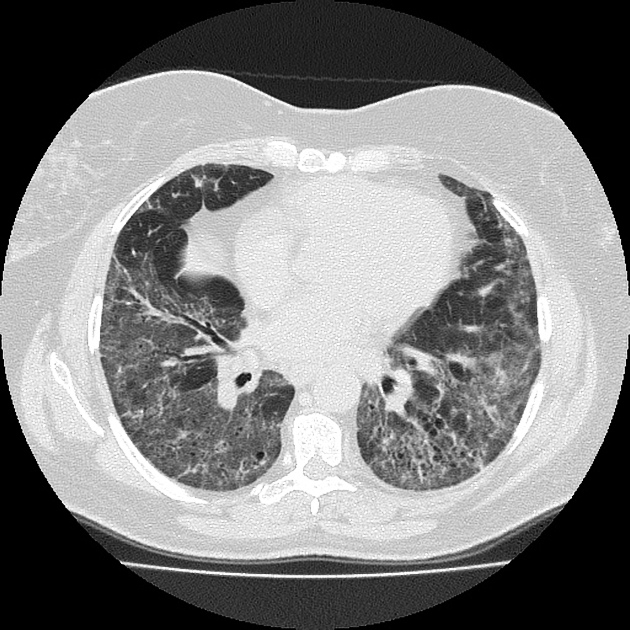

Where is the predominance of NSIP?

Lower lobes, posterior and peripheral predominance with sparring of the immediate subpleural spaces.

immediate subpleural sparing - a relatively specific sign

List the differences between NSIP and UIP:

NSIP:

UIP: